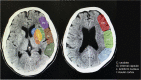

Delayed cerebral ischaemia (DCI) is a significant complication of aneurysmal subarachnoid haemorrhage (aSAH) and is strongly associated with poorer outcome. The Alberta Stroke Program Early Computer Tomography (ASPECT) score is an established scoring tool, used in acute ischaemic stroke, to quantify early ischaemic changes on CT head scans. We aim to identify if ASPECT scoring correlates with functional outcome in DCI following aSAH. Retrospective case-control study. Inclusion criteria: admission to the Department of Neurosurgery at Leeds Teaching Hospitals NHS Trust (a tertiary neurosurgical centre in the United Kingdom) between 2014 and 2018, with a diagnosis of anterior circulation aneurysmal subarachnoid haemorrhage; as confirmed by initial CT scan and subsequent CT angiography or catheter digital subtraction angiography. Cases were those who developed DCI (n = 43) and controls were randomly selected from those who did not develop DCI (n = 46) but otherwise met the same inclusion criteria. The primary outcome measure was Glasgow Outcome Score (GOS): assessed at discharge and 3 months. ASPECT scores were calculated from non-contrast CT head scans by three researchers blinded to each other and clinical outcome. Spearman's rank correlation was used to calculate correlation between ASPECT scores and GOS. ASPECT score positively correlated with GOS in the cases both at discharge (Spearman rho 0.436, p = 0.003) and at 3 months (Spearman rho 0.431, p = 0.004). When corrected for Fisher grading, the adjusted odds ratio of having a high GOS with a low ASPECT score at discharge was OR 0.74 (95% CI 0.61-0.94, p = 0.003), and 3 months OR 0.73 (95% CI 0.59-0.91, p = 0.005). ASPECT score significantly correlates with clinical outcome in DCI post aSAH, even after correcting for Fisher grade. ASPECT scoring may identify patients at risk of poor outcome following DCI and represents a quick and reliable tool that aids in clinical decision-making and prognostication.